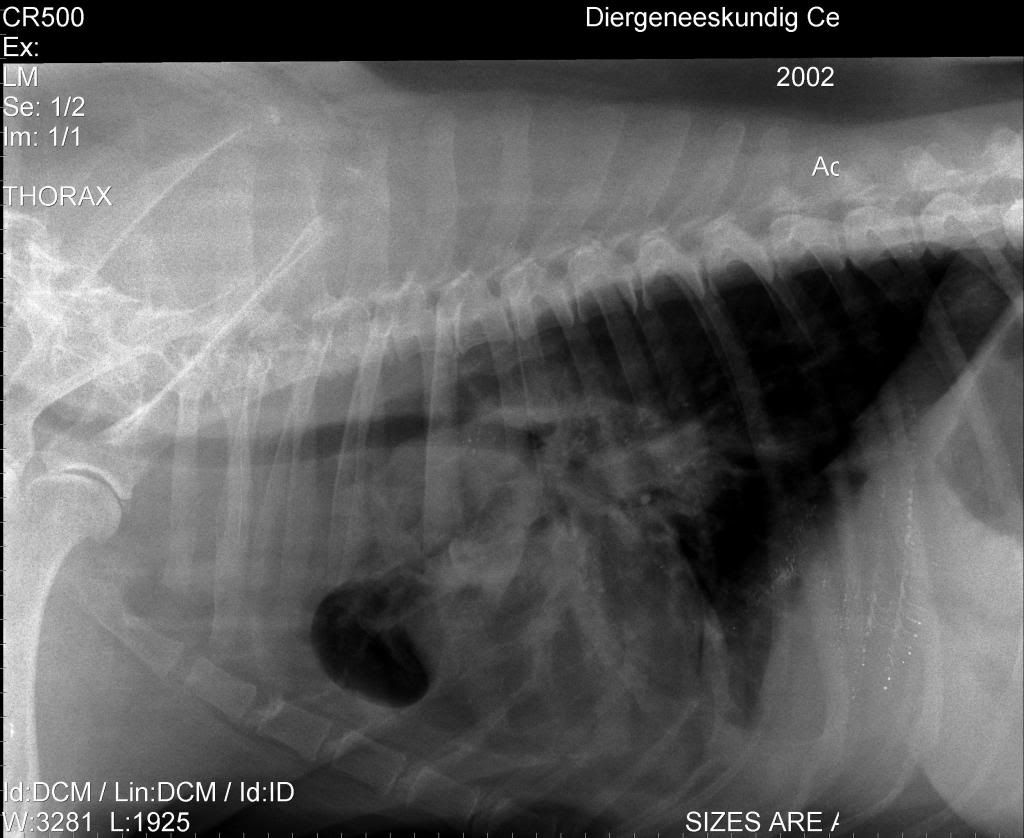

Ben benieuwd wat jullie denken te zien

Dat is ook wat ik er in zie, meer kan ik er niet van maken.Jeannettebo schreef:Rechterlong ziet er niet lekker uit...en wellicht een wat groot hart?

Denk dat jij in de goede richting zit. Moet er wel bij zeggen dat ze kennelhoest heeft en dan de zware vorm en tegen een longontsteking aan zit.Jeannettebo schreef:Rechterlong ziet er niet lekker uit...en wellicht een wat groot hart?

Ik denk dat de longontsteking er al zit, rechts meer dan links, links begint in een bovenkwabDemi schreef:Denk dat jij in de goede richting zit. Moet er wel bij zeggen dat ze kennelhoest heeft en dan de zware vorm en tegen een longontsteking aan zit.Jeannettebo schreef:Rechterlong ziet er niet lekker uit...en wellicht een wat groot hart?

Over welke foto heb je het dan? De dierenarts waar ik net was deed erg moeilijk en gaf ons het gevoel ga maar lekker naar huis met je oude hond. Toen ik vroeg of ze geen ab moest hebben voor de longontsteking was het antwoord nee en ik kreeg dexametason en plaspillen meeJeannettebo schreef:Ik denk dat de longontsteking er al zit, rechts meer dan links, links begint in een bovenkwabDemi schreef:Denk dat jij in de goede richting zit. Moet er wel bij zeggen dat ze kennelhoest heeft en dan de zware vorm en tegen een longontsteking aan zit.Jeannettebo schreef:Rechterlong ziet er niet lekker uit...en wellicht een wat groot hart?

TARAKfreskin schreef:Ik heb totaal geen verstand van rontgenfoto's, maar dit ziet er niet goed uit, volgens mij. De rechterlong lijkt bijna helemaal geen lucht meer te bevatten, maar een ruimte innemend proces of ontsteking/verbindweefseling. Het hart lijkt me inderdaad ook vergroot. Maar dit is voor mij echt gissen..... Ik zou inderdaad zo snel mogelijk een longspecialist inschakelen.